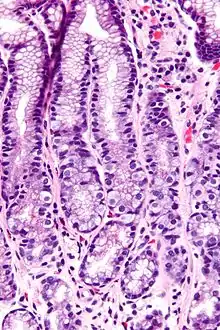

Microfotografia do antro gástrico mostrando um grande número de células G, com forma semelhante a ovos estrelados.

A célula G é um tipo de célula do antro gástrico, parte afunilada do estômago, que secreta gastrina, hormônio protéico liberado na ingestão de alimentos com alto teor protéico. Atua na mucosa gástrica estimulando células parietais a liberarem HCl.[1]